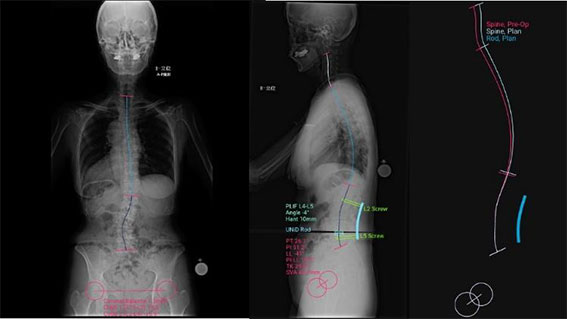

UNiDTM ASIでは、患者様一人ひとりに適したロッド形状を設計し、この設計データをMAZOR Xのプランニングソフトに取り込み(図4・5)、術前の設計通りにスクリューをロボットが自動で誘導することで、ロッドとスクリューの適合精度をさらに高めることが可能となりました。

【図4】 MAZOR Xのプラニングソフト(UNiD ロッド適応前)

スクリューは正確な位置に配置済み。

【図5】 MAZOR Xのプラニングソフト(UNiD ロッド適応後)

予測される脊椎の矯正状態を確認できる。